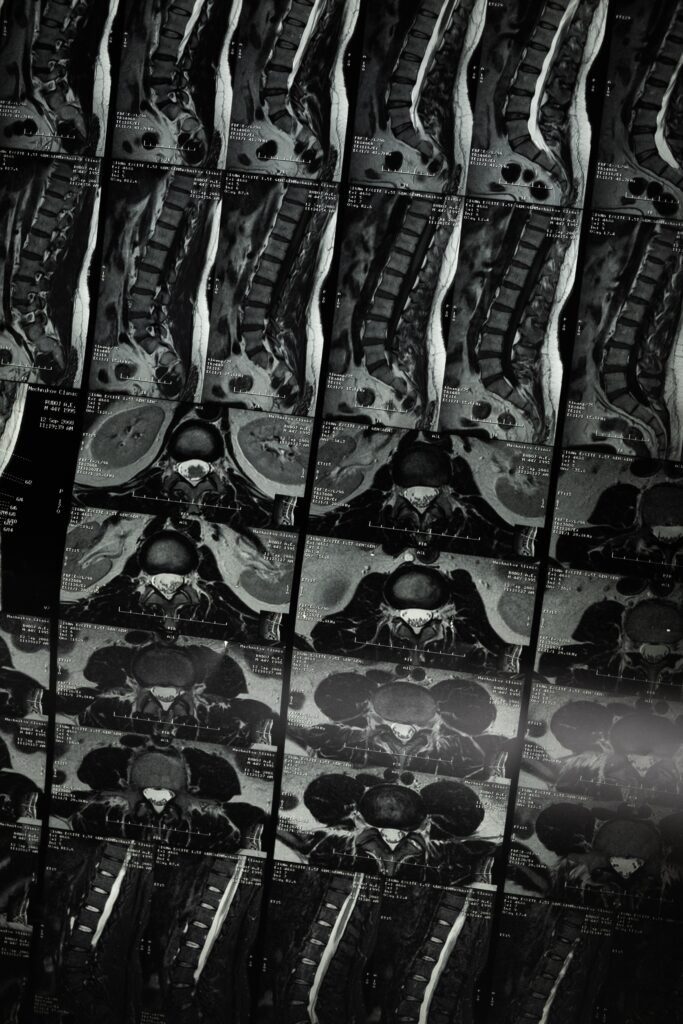

Dijagnoza i liječenje: Dijagnoza spondiloze vratne kralježnice obično se postavlja temeljem medicinske povijesti, fizikalnog pregleda i radioloških pretraga kao što su rendgenske snimke, magnetska rezonanca (MRI) ili kompjutorska tomografija (CT).

- Dijagnoza i liječenje: Dijagnoza spondiloze lumbalne kralježnice obično se postavlja temeljem medicinske povijesti, fizikalnog pregleda i radioloških pretraga kao što su rendgenske snimke, magnetska rezonanca (MRI) ili kompjutorska tomografija (CT). Liječenje može uključivati konzervativne metode poput fizikalne terapije, lijekova protiv bolova, injekcija ili kirurškog zahvata u težim slučajevima.

Dijagnoza i liječenje: Dijagnoza spondiloze torakalne kralježnice obično se postavlja temeljem medicinske povijesti, fizikalnog pregleda i radioloških pretraga kao što su rendgenske snimke, magnetska rezonanca (MRI) ili kompjutorska tomografija (CT). Liječenje može uključivati konzervativne metode poput fizikalne terapije, lijekova protiv bolova ili injekcija, a u težim slučajevima može se razmotriti kirurško liječenje.

- Radiološke pretrage: Uključujući rendgenske snimke, magnetsku rezonancu (MRI) i kompjutorsku tomografiju (CT) radi preciznog prikaza kralježnice i degenerativnih promjena.